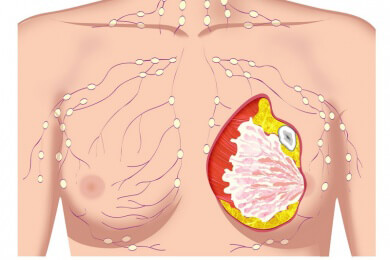

Normalerweise beginnt die Menopause bei den Frauen zwischen dem 42. und 58. Lebensjahr. Der genaue Zeitpunkt kann aber über die vorhandenen Eizellen und der Größe der Eierstöcke bestimmt werden.

Im Alter von 37 Jahren besitzt eine Frau durchschnittlich noch 25.000 Eizellen, bis zum Beginn der Wechseljahre sinkt diese Zahl auf etwa 1.000.